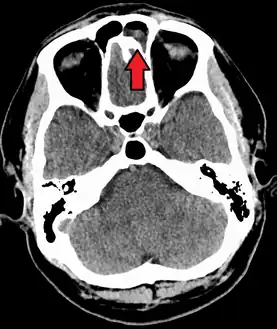

The proximity of the brain to the sinuses makes the most dangerous complication of sinusitis, particularly involving the frontal and sphenoid sinuses, infection of the brain by the invasion of anaerobic bacteria through the bones or blood vessels. Abscesses, meningitis, and other life-threatening conditions may result. In extreme cases, the patient may experience mild personality changes, headache, altered consciousness, visual problems, seizures, coma, and possibly death.[16]

Sinus infection can spread through anastomosing veins or by direct extension to close structures. Orbital complications were categorized by Chandler et al. into five stages according to their severity (see table).[26] Contiguous spread to the orbit may result in periorbital cellulitis, subperiosteal abscess, orbital cellulitis, and abscess. Orbital cellulitis can complicate acute ethmoiditis if anterior and posterior ethmoidal veins thrombophlebitis enables the spread of the infection to the lateral or orbital side of the ethmoid labyrinth. Sinusitis may extend to the central nervous system, where it may cause cavernous sinus thrombosis, retrograde meningitis, and epidural, subdural, and brain abscesses.[27] Orbital symptoms frequently precede intracranial spread of the infection . Other complications include sinobronchitis, maxillary osteomyelitis, and frontal bone osteomyelitis.[28][29][30][31] Osteomyelitis of the frontal bone often originates from a spreading thrombophlebitis. A periostitis of the frontal sinus causes an osteitis and a periostitis of the outer membrane, which produces a tender, puffy swelling of the forehead.

The diagnosis of these complications can be assisted by noting local tenderness and dull pain, and can be confirmed by CT and nuclear isotope scanning. The most common microbial causes are anaerobic bacteria and S. aureus. Treatment includes performing surgical drainage and administration of antimicrobial therapy. Surgical debridement is rarely required after an extended course of parenteral antimicrobial therapy.[32] Chronic sinus infections may lead to mouth breathing, which can result in mouth dryness and an increased risk of gingivitis. Decongestants may also cause mouth dryness.[33]

Infection of the eye socket is a rare complication of ethmoid sinusitis, which may result in the loss of sight and is accompanied by fever and severe illness. Another possible complication is the infection of the bones (osteomyelitis) of the forehead and other facial bones – Pott's puffy tumor.[16]